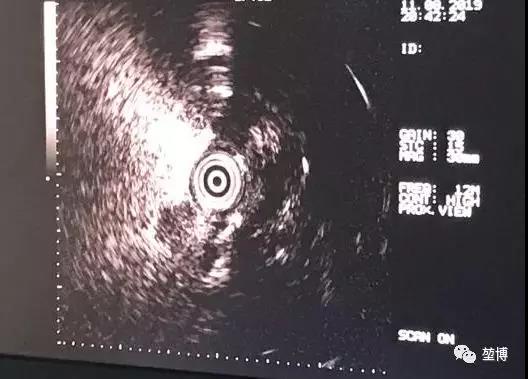

术中,根据LungPro导航术前规划的路径,导航实时引导支气管镜抵达靶点部位附近,先用超声确认抵达病灶位置,再将激光光纤送入术前规划部位,进行消融。

送入超声探头

超声确认抵达病灶